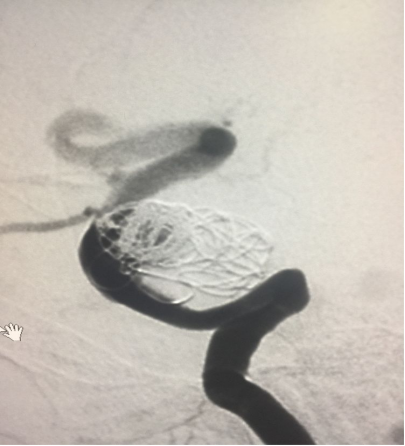

帯毛圈也填了,“子弹”打光后(密网支架十5个圈)最后造影

最后应用J型导丝及球囊将下方支架充分打开并贴壁,正位片所见